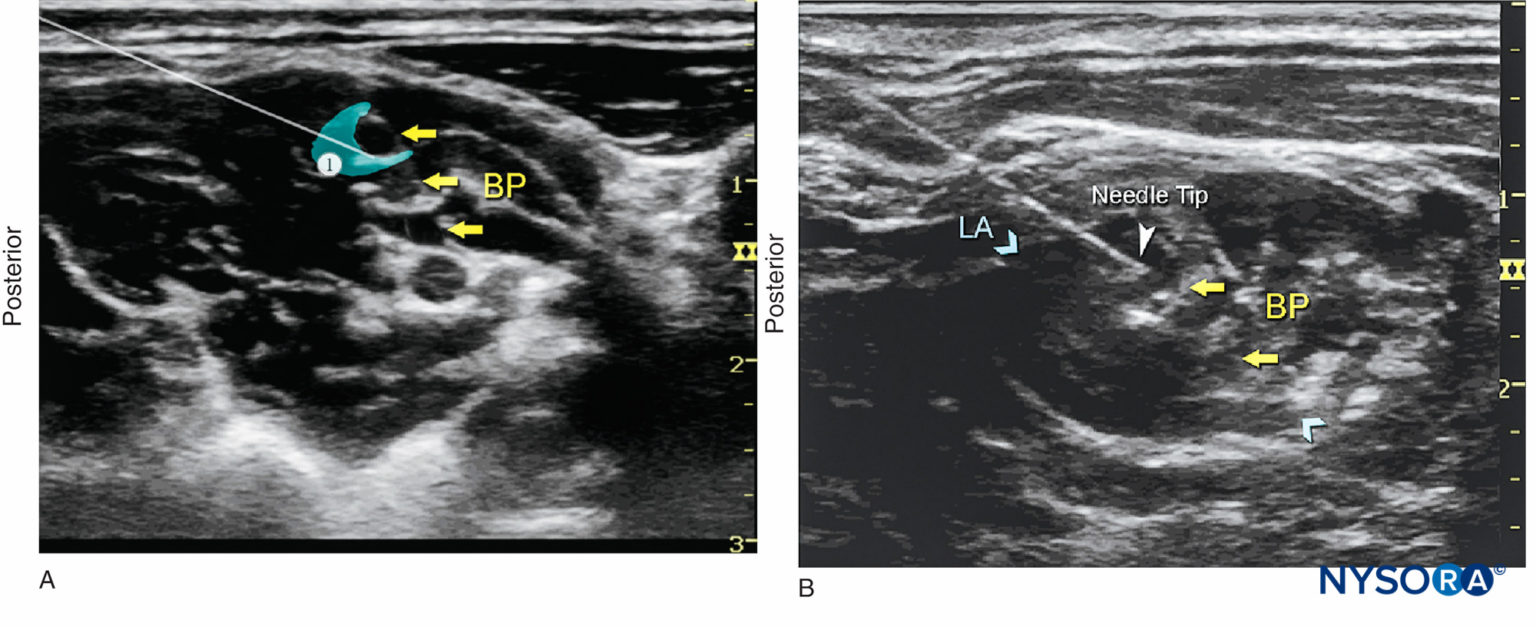

From www.nysora.com

UltrasoundGuided Interscalene Brachial Plexus Nerve Block NYSORA What Is Interscalene Block the interscalene block (isb) anesthetizes the brachial plexus at the level of the nerve roots, and is used for surgery. the part of the brachial plexus that supplies your shoulder sits in a “groove” in your neck called the interscalene groove. The brachial plexus is commonly blocked at interscalene level for surgeries involving. the interscalene nerve block. What Is Interscalene Block.

UltrasoundGuided Interscalene Brachial Plexus Nerve Block NYSORA What Is Interscalene Block the part of the brachial plexus that supplies your shoulder sits in a “groove” in your neck called the interscalene groove. The brachial plexus is commonly blocked at interscalene level for surgeries involving. the interscalene block is indicated for procedures on the shoulder and proximal humerus as well as the lateral two thirds of the clavicle. interscalene. What Is Interscalene Block.

UltrasoundGuided Upper Extremity Blocks NYSORA What Is Interscalene Block The brachial plexus is commonly blocked at interscalene level for surgeries involving. the interscalene nerve block is a commonly performed regional anesthetic technique at the level of the upper trunks of the brachial plexus to. the interscalene block is indicated for procedures on the shoulder and proximal humerus as well as the lateral two thirds of the clavicle.. What Is Interscalene Block.